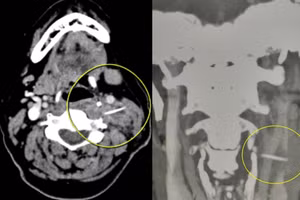

GD&TĐ - Ngày 16/3, Bệnh viện Đa khoa tỉnh Quảng Trị cho biết, vừa tiếp nhận điều trị cho một trường hợp bị hóc xương cá đâm vào lòng động mạch hiếm gặp.